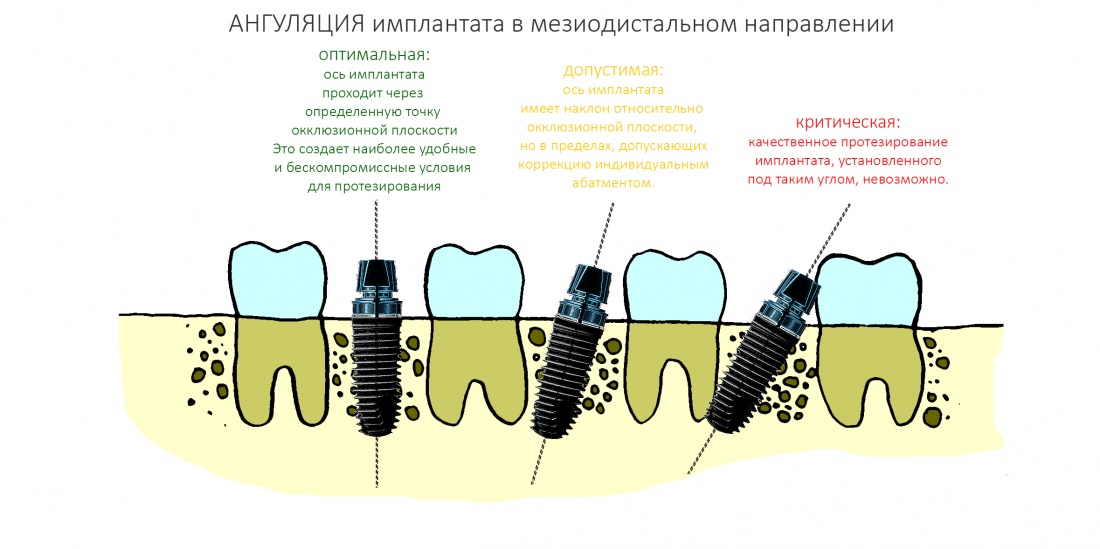

Я разделяю ангуляцию на , оптимальную, допустимую и критическую. Разницу между ними поясняет картинка ниже:

Ангуляция — это наш союзник и наш враг. С одной стороны, изменением наклона оси имплантата мы можем исправить изначально неправильное позиционирование по окклюзионной плоскости. С другой стороны, критической ангуляцией можно испортить даже правильно установленный по плоскости имплантат. В общем, хитрая это штука, и рассматривать её мы будем в контексте общего позиционирования.

Гораздо менее понятная штука — это ангуляция имплантата, т. е. угол, образуемый осью импланта и акклюзионной плоскостью альвеолярного гребня.

Если бы челюстная кость имела бы правильную геометрическую форму (например, параллелепипеда), то не было бы нужды рассматривать ангуляцию — мы ставили все наши имплантаты под углом 90 градусов к окклюзионной плоскости, и было бы всем счастье:

Чуть выше я уже говорил, что ангуляция может быть оптимальной, допустимой и критической. Последняя делает протезирование на таком импланте просто невозможным:

Суть в том, чтобы при установке имплантата его ось оставалась в пределах конуса, описываемого допустимой ангуляцией, а в идеале — в пределах описываемого оптимальной: